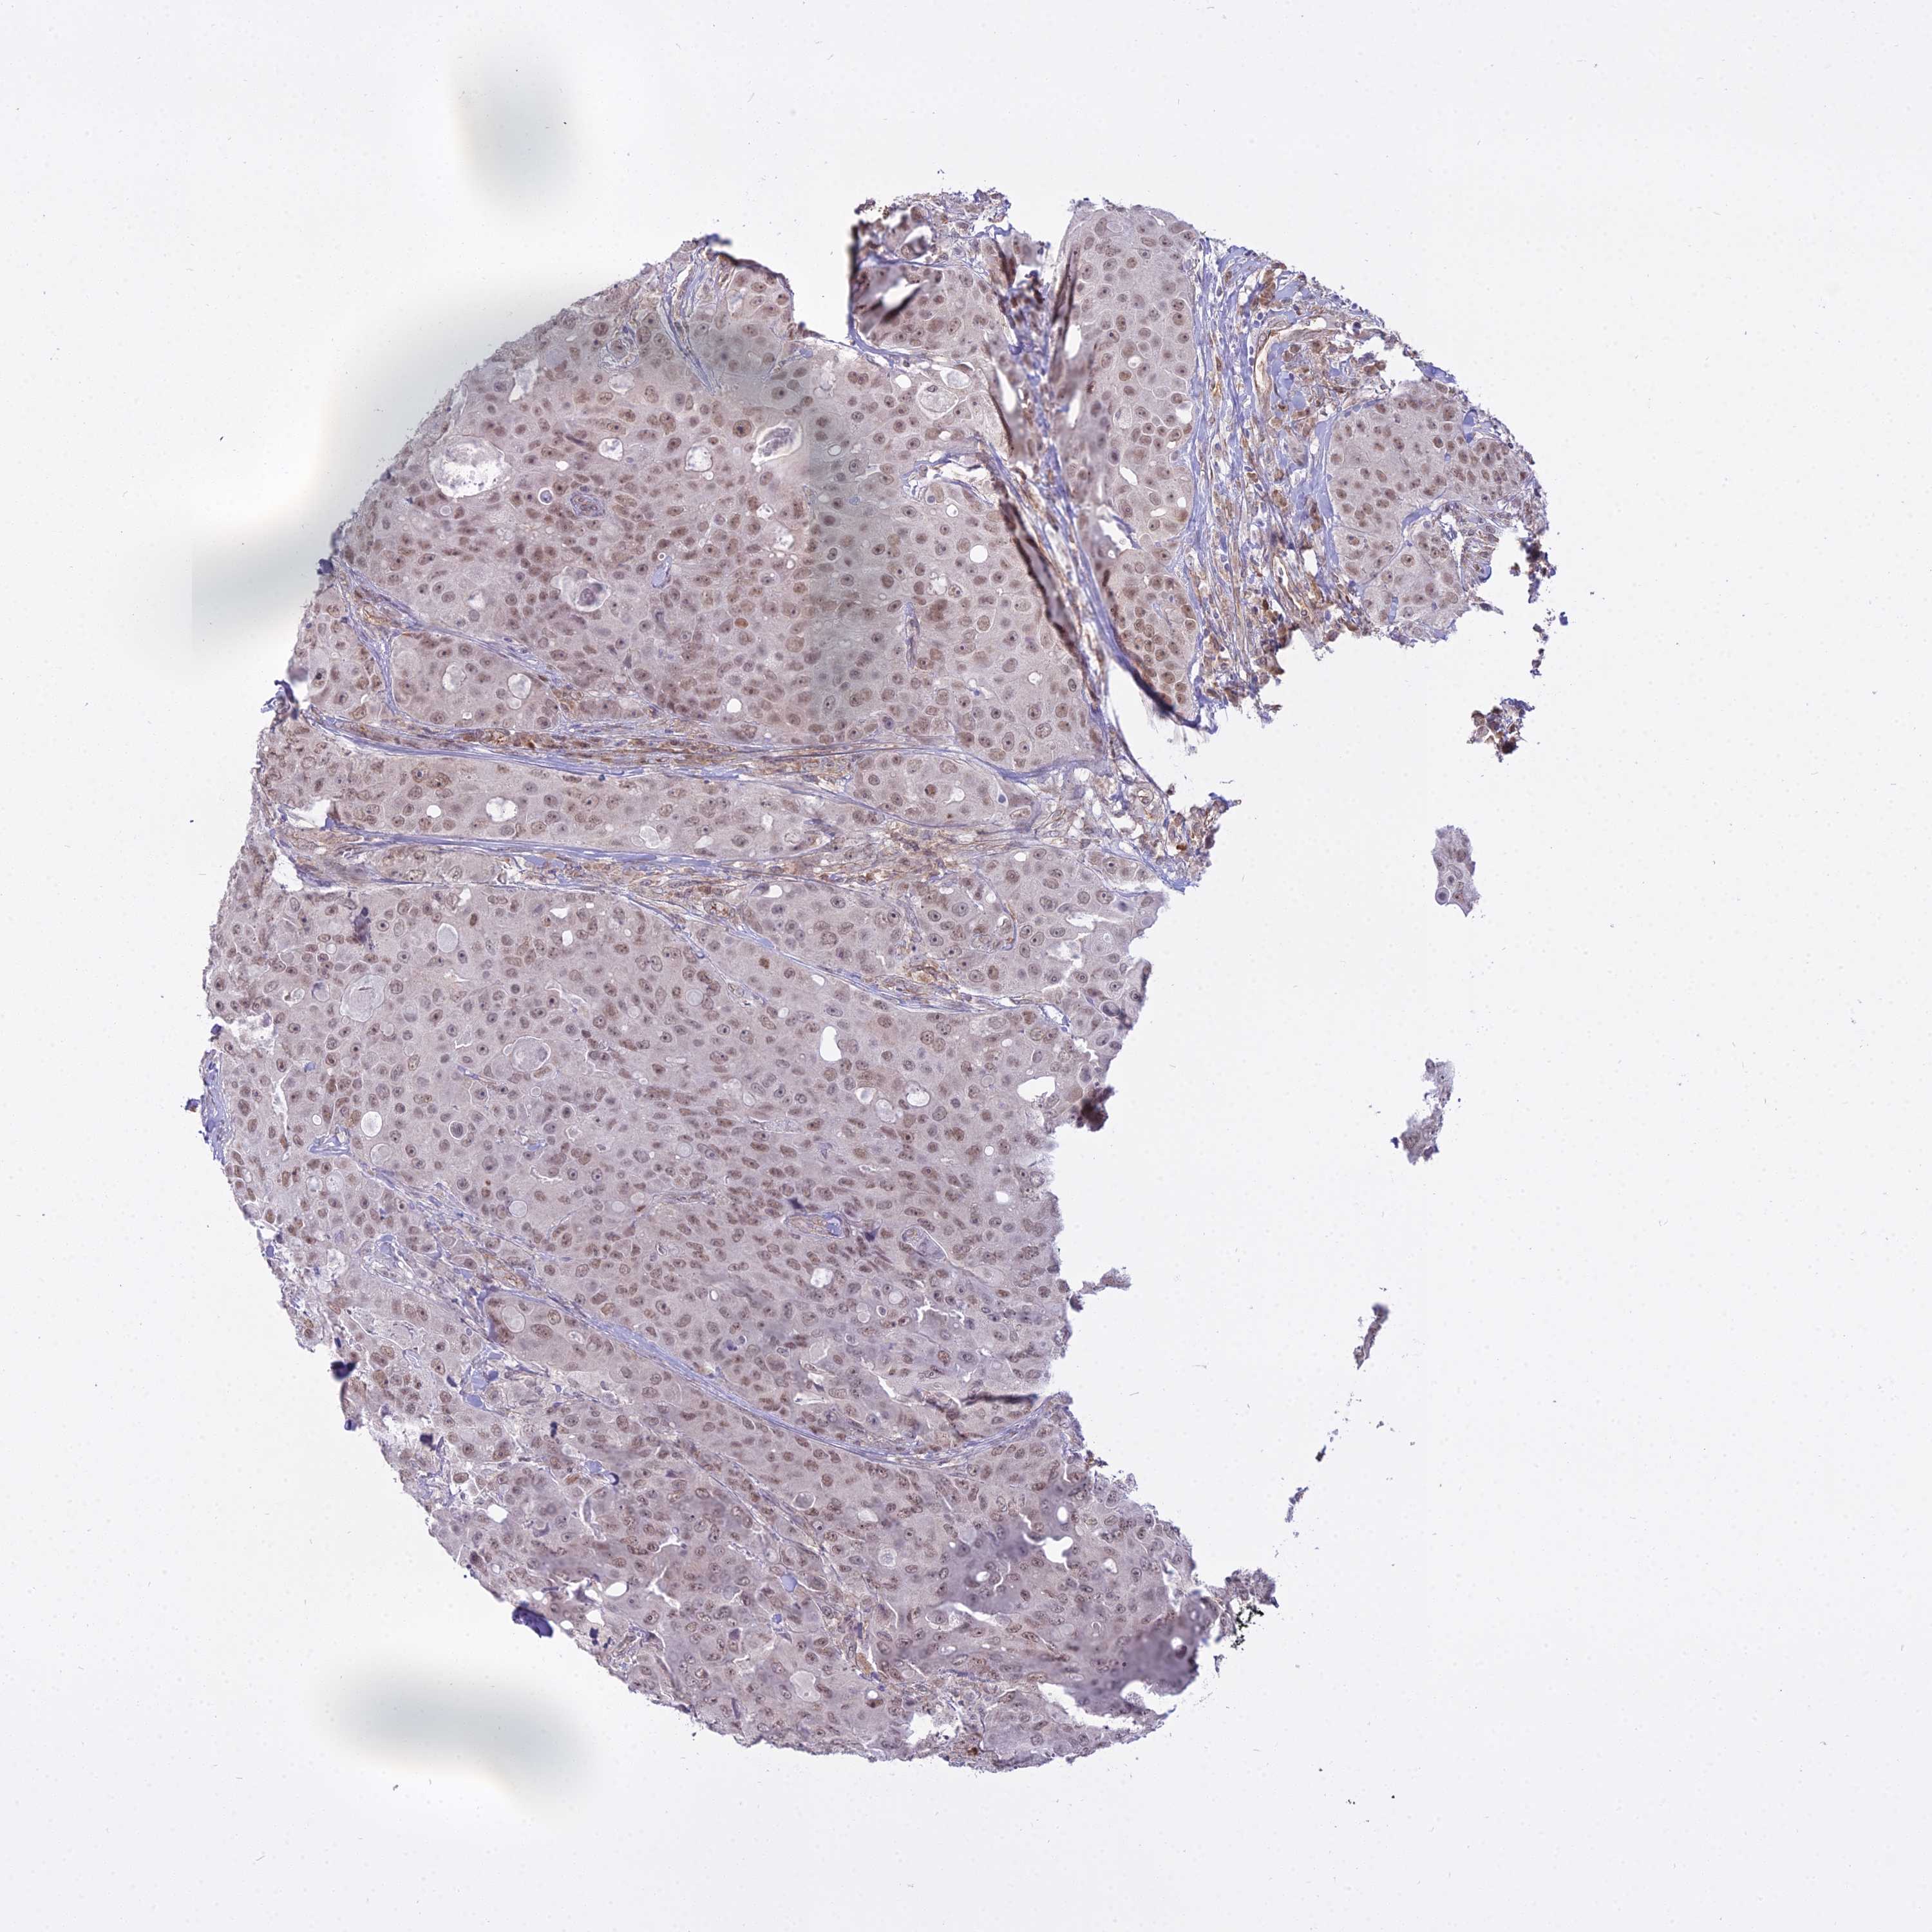

CANCER BREAST CANCER Show tissue menu

BRCA TCGA BRCA VALIDATION PROTEIN EXPRESSION